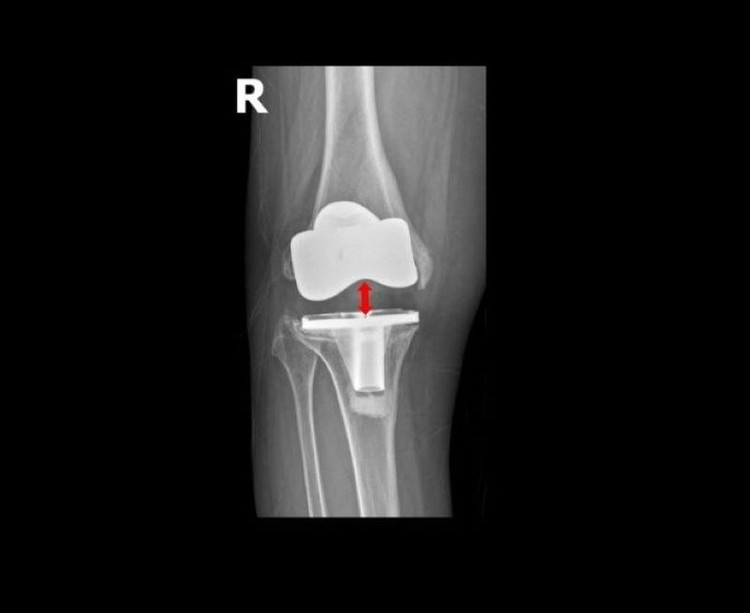

Khớp gối nhân tạo lỏng lẻo, di lệch khỏi ổ khớp - Ảnh BVCC

Khớp gối nhân tạo lỏng lẻo, di lệch khỏi ổ khớp

TS.BS Lê Quang Huy, Trưởng khoa Ngoại Chấn thương chỉnh hình - Thần kinh sọ não, Bệnh viện Đa khoa Hồng Ngọc - Phúc Trường Minh cho biết: "Trường hợp của bệnh nhân Oanh hiếm gặp.

Chỉ sau gần 5 năm phẫu thuật, cấu phần lồi cầu đùi nhân tạo (phần kim loại bao bọc đầu dưới xương đùi) đã lún vào lồi cầu trong xương đùi gần 2cm, khiến khớp gối lệch khỏi vị trí ban đầu, mất vững kèm mất cân bằng mô mềm quanh khớp dẫn đến bệnh nhân không đi lại được.

Các nguyên nhân gây biến chứng như nhiễm trùng hay viêm xương tuỷ đã được chúng tôi loại trừ, có thể do cơ địa bệnh nhân không phù hợp với loại khớp cấy ghép, tình trạng loãng xương nặng gây tiêu xương hoặc kỹ thuật cắt xương chưa thực sự chuẩn xác. Giải pháp duy nhất để phục hồi vận động và ngăn ngừa nguy cơ tàn phế là phẫu thuật thay lại khớp gối”.